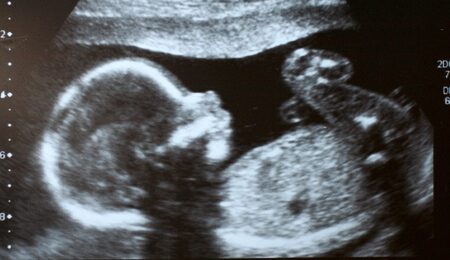

nienarodzony-5-lifeaction-org.jpg

Fot. LifeAction.org